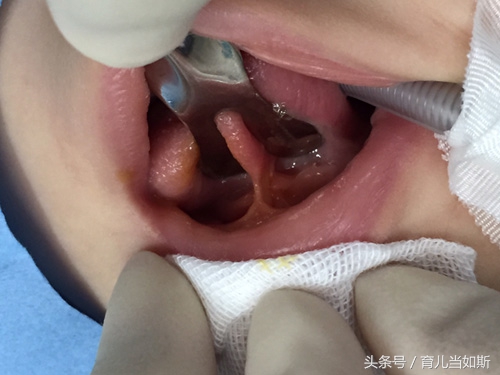

我们平时伸舌头时,舌尖呈锥形,宝宝也是如此。如果发现宝宝伸舌头的时候,舌尖呈“M”形或“W”形,也就是舌尖端凹陷,舌头不能自由的前伸,则说明舌系带过短。 舌系带过短的危害:新生儿哺乳困难;大宝宝说话不清。

小宝宝的牙齿还未萌出,牙床还是低平的,所以舌系带看起来很短的样子。这个时候妈妈们先不要着急,如果宝宝吃奶不困难,可以等到宝宝前乳牙萌出后观察一下,一般在7、8个月左右时候会萌出。舌系带会随着牙齿的萌出而发生变化,往后和往下退缩、变长。所以,检查舌系带是否过短应该至少在宝宝下前乳牙萌出以后。